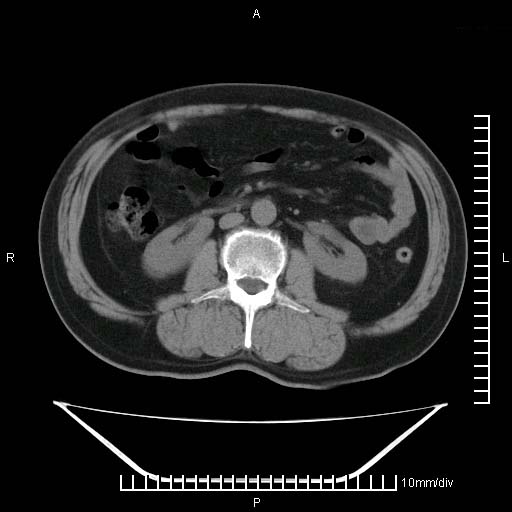

标题: CT25082:肝脏增强:男性,70岁 [打印本页]

标题: CT25082:肝脏增强:男性,70岁

患者以心脏疾病收住院,腹部无明显症状,b超查肝脏有占位。

增强效果不理想。考虑转移,胆囊壁明显增厚,不排除胆囊癌肝转移。

牛眼征,中心坏死无强化,外缘强化,最外缘又见低密度,考虑转移,与脓肿鉴别

肝内多发转移瘤,右下肺炎症并少量胸水。胃壁增厚建议胃镜,胰尾部“病变”为肠管。

1)肝脏多发性转移瘤(不排除胰尾癌转移所致可能)。2)腹水。3)右侧少量胸腔积液。

ct25082 结果:转移瘤

外院mr结果:胰尾恶性占位。